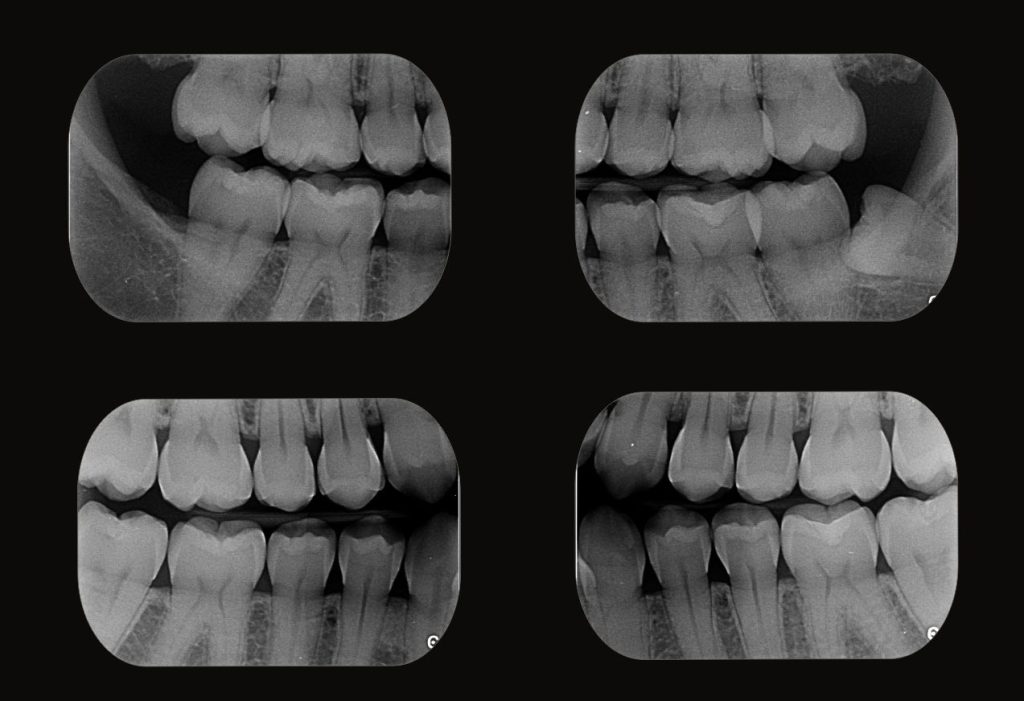

Radiografia Interproximal

Exame de precisão para diagnóstico de cáries e avaliação periodontal

A radiografia interproximal, também chamada de bite-wing, é um exame odontológico essencial para a detecção de cáries em superfícies proximais, avaliação da adaptação de restaurações e monitoramento da crista óssea alveolar. Esse exame é amplamente utilizado na odontologia preventiva, restauradora e periodontia, proporcionando diagnósticos mais precoces e detalhados.